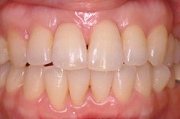

CASE2

↓前歯の歯並びを きれいに治したい。

(35歳/女性)

|||||||||

概要・担当医コメント:叢生・審美障害↑

動的治療期間13ヶ月(12回)/非抜歯/費用概算:55万円

上は固定式のブラケット矯正で,下は患者様ご自身が着脱するマウスピース矯正の治療を行いました.治療結果には大変満足されているそうです.